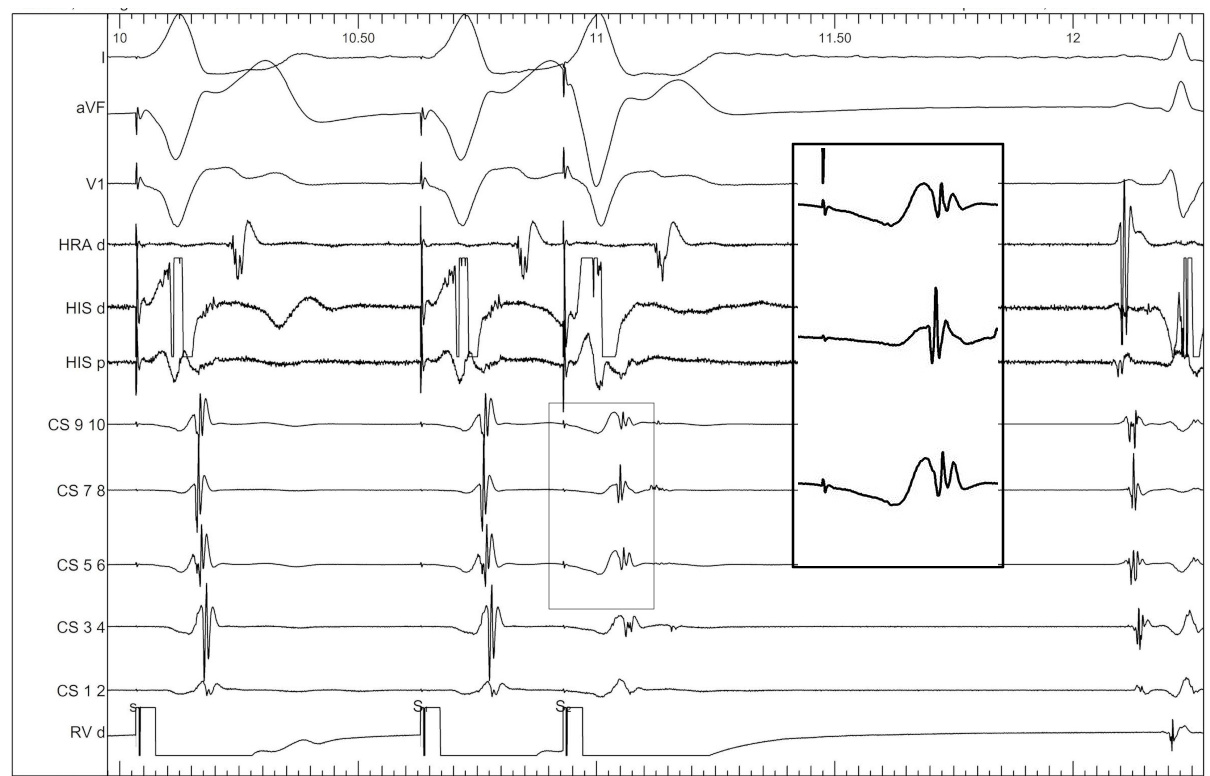

Use triggered mode

trigger.jpg

Use unipolar EGMs

uni.jpg

Identify components of the signal

mask1.jpg

mask2.jpg

mask3.jpg

mask4.jpg